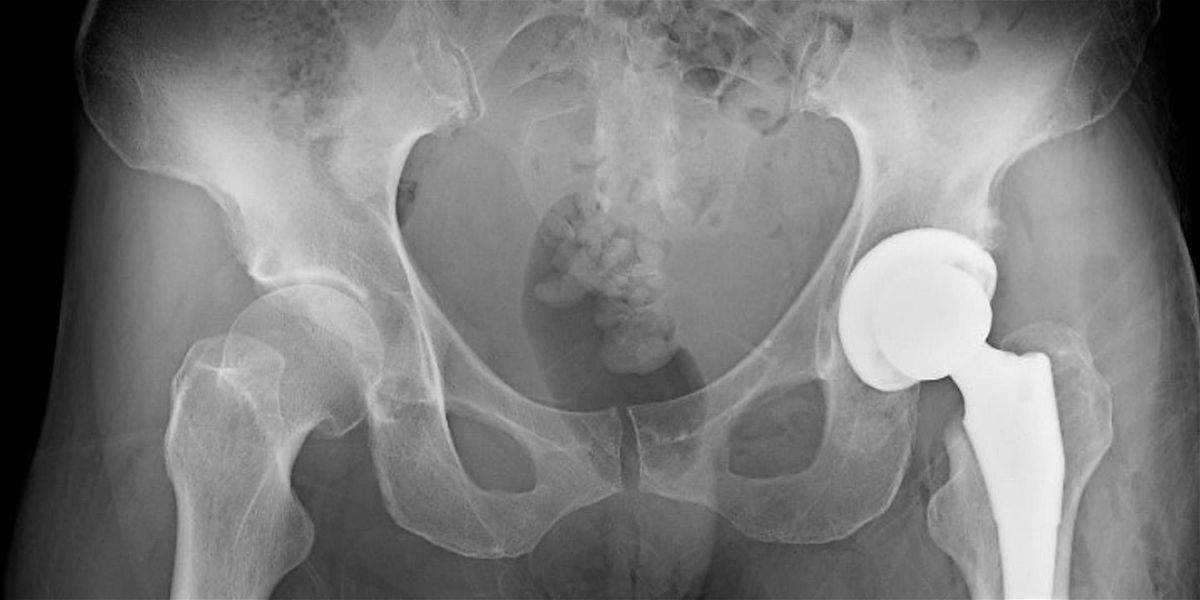

- **Event Description**: Insights on pre-total hip replacement considerations and the elements important for success when getting back to dance post-procedure.About this EventHarkness Center for Dance Injuries proudly offers in-person and virtual Harkness Center Saturday Series workshops for the dance community.DECEMBER 2025 WORKSHOPTopic: Total Hip Replacement: Preparation and Return to DanceWhen: Saturday, December 6, 2025 at 11:00 AM ESTFormat: VIRTUAL (Zoom)Description: Getting a total hip replacement (THR) is a major life decision. Dancers considering and pursuing this procedure often navigate complex emotions as well as logistics. But the recovery process and post-surgery career and life can be rewarding and even transformative.Physical therapist Dr. Sarah Plumer-Holzman specializes in treating the hip at the Harkness Center for Dance Injuries. In this virtual Saturday Series workshop, she will offer insights on pre-THR considerations and the elements important for success when getting back to dance post-procedure.Instructor: Sarah Plumer-Holzman, PT, DPT holds a bachelor of fine arts from the North Carolina School of the Arts and a doctorate in physical therapy from the University of Washington. A board-certified orthopedic clinical specialist, she is also a certified functional manual therapist through the Institute of Physical Arts. Previously, Dr. Plumer-Holzman danced professionally in New York City for nine years, performing in both modern and contemporary ballet companies. She has studied with choreographer and anatomist Irene Dowd since 2000, assisting her for five years. Dr. Plumer-Holzman has been a dedicated yoga practitioner and teacher in the Ashtanga yoga tradition for more than 25 years and has taught anatomy and kinesiology for yoga teachers since 2006.Saturday Series workshops are led by our clinical staff and feature various topics on dancer wellness and injury prevention. All members of the dance community are welcome (dancers under age 16 are strongly encouraged to come with a parent/guardian*). Please note whether format is in-person or virtual.*We strongly encourage participants under 16 years of age to attend with a parent/guardian. If a parent/guardian plans to drop off a minor, please make sure you have corresponded with the Harkness Center in advance.Liability waiver: for workshops that include movement, participants will be required to sign a liability waiver.Refund policy: We cannot provide refunds after the event has taken place. Eventbrite fees cannot be refunded.Questions: Contact Kristen Stevens, program manager, Kristen.Stevens@nyulangone.orgUpcoming Harkness Events:Stay tuned for our 2026 Saturday Series lineup!About the Harkness Center for Dance Injuries: NYU Langone's Harkness Center for Dance Injuries (www.DanceInjury.org) is dedicated to enhancing the health and well-being of dance professionals by providing breakthrough approaches to injury prevention, medical treatment, education and training, and research. Founded in 1989 through a partnership between the Harkness Foundation for Dance and the Hospital for Joint Diseases (now NYU Langone Orthopedic Hospital), the Harkness Center provides world-class clinical care for dancers of all types and levels. The scientific foundation for this expert care comes from research into understanding the dancer’s body in motion coupled with workplace requirements. The Harkness Center’s evidence-based practice has produced globally accepted approaches to the recognition, treatment, and prevention of dance injuries.In addition to caring for injuries, an integral part of the Harkness Center’s mission is providing education. For the dance community, Harkness offers injury prevention workshops, online courses, and screenings, including its long-running, free Injury Prevention Assessment (IPA) program. For fellow dance medicine professionals, Harkness is actively engaged in sharing clinical best practices through academic training with live and online continuing education courses. Since 2015, Harkness Center has offered DanceMedU, its digital learning platform (www.DanceMedU.org), which now offers over 20 lectures on dance medicine and dancer health.